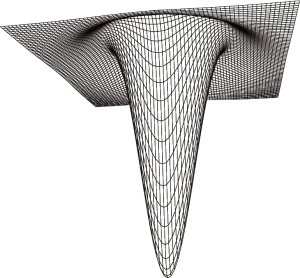

The shape of the LoG filter convolution matrix is similar to a “reversed Mexican hat” as shown in Figure 1.